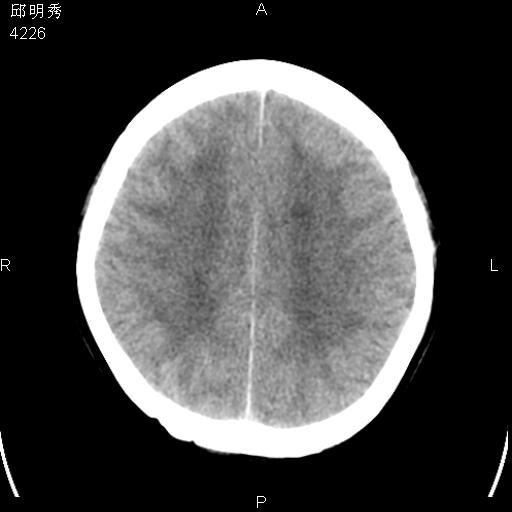

40f头晕十多天,右上肢麻木一天

脑白质变性或ms

脑白质脱髓鞘改变。

脑白质病;建议行mri检查。